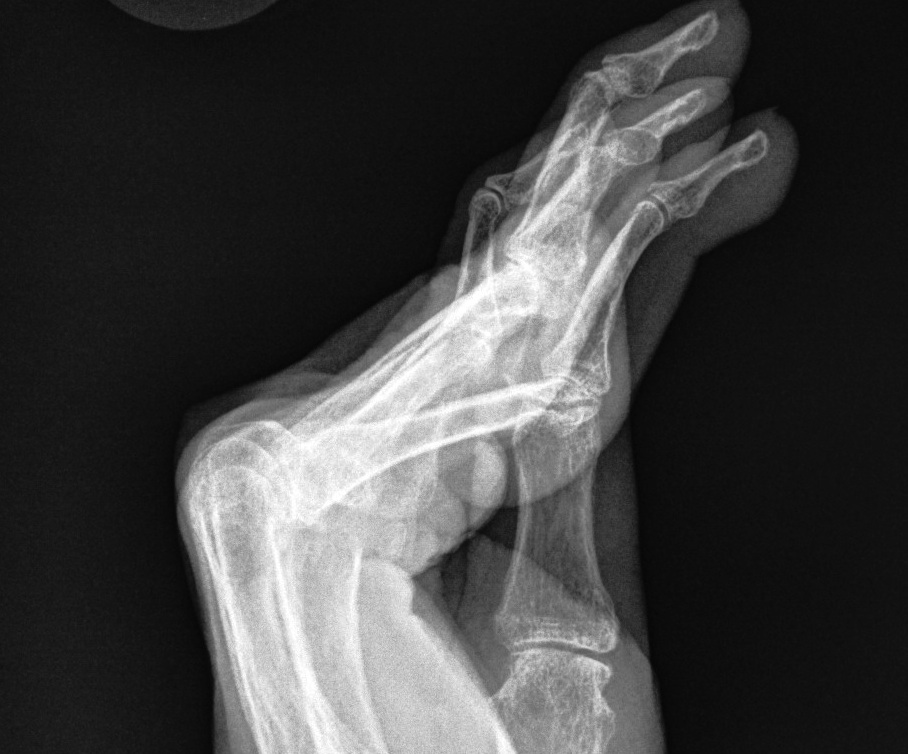

Swan Neck Deformity (Intrinsic Plus Deformity)

Hyperextended PIPJ / MCPJ + DIPJ flexion

- Bunnell calls this "Intrinsic plus deformity"

Primary process is usually synovitis

- starts at either MCPJ / PIPJ / DIPJ